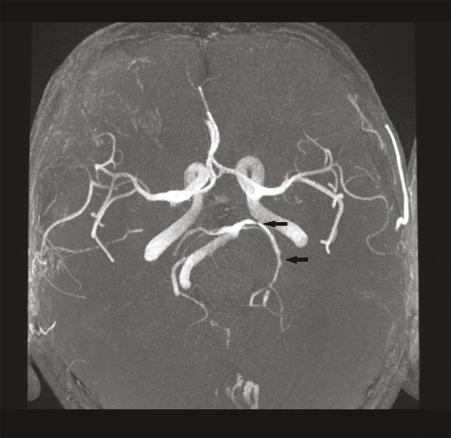

Cet homme de 71 ans est hospitalisé en mars 2020 pour un accident vasculaire cérébral ischémique (AVCi) de la capsule interne gauche (fig. 1 ) d’évolution favorable. L’enquête étiologique est négative mais des causes cardiovasculaires sont considérées comme probables. Après un épisode de céphalées intenses, mal calmées par le paracétamol, le patient est réhospitalisé en urgence début juillet pour une hémiplégie gauche ; l’imagerie révèle un aspect de vascularite cérébrale des gros troncs (fig. 2 ). La maladie de Horton est éliminée. Mi-juillet, un nouvel AVCi se traduit par une aggravation de l’hémiplégie gauche, une confusion mentale, une ataxie. Des échanges téléphoniques et écrits orientent alors vers le diagnostic de borréliose ; la ponction lombaire (95 % de lymphocytes, 8 hématies, protéinorachie 0,93 g/L, IgG anti Borrelia Burgdorferi > 240 UA/mL) et le profil sérologique de la maladie de Lyme (IgG 352 et IgM 2,3 UA/mL en faveur d’une infection semi-récente) confirment la neuro-borréliose active tardive (index de sécrétion intrathécale de 3,3 donc > 2) sous forme d’une méningo-vascularite.1 Un traitement par doxycycline est débuté puis le patient est pris en charge par un service de rééducation fonctionnelle dédié, avec d’importantes séquelles.